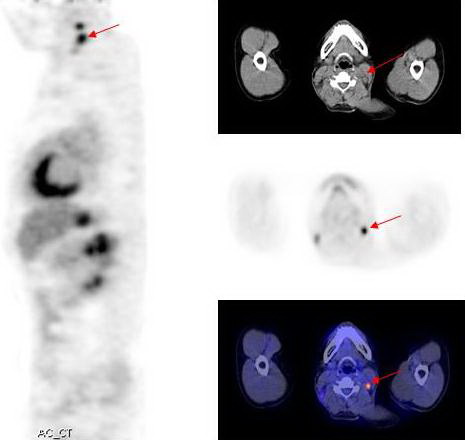

Hình 1: Hình ảnh PET tổng thể cho thấy các tổn thương tăng hấp thu

FDG bất thường tại các vị trí mũi tên

Hình 3: Hình ảnh PET/CT cho thấy tổn thương di căn hạch cổ trái.

Kết quả PET/CT: tổn thương tăng hấp thu FDG mạnh tại vòm họng bên trái, max SUV=11,8, các tổn thương di căn hạch tại vùng cổ bên phải và bên trái.

Trong khi đó kết quả nội soi vòm họng và CT không phát hiện thấy tổn thương u nguyên phát (CT-) bởi vì tổn thương ở mức độ chưa xâm lấn ra bề mặt niêm mạc vòm họng và mà mắt chưa thể nhận thấy được  qua  nội soi, CT...

Dựa vào các kết quả trên, bệnh nhân được chẩn đoán là ung thư vòm họng di căn hạch cổ hai bên. Đồng thời đánh giá được giai đoạn bệnh của bệnh nhân là T1N2M0, kế hoạch điều trị tiếp theo là xạ trị phối hợp hoá trị.